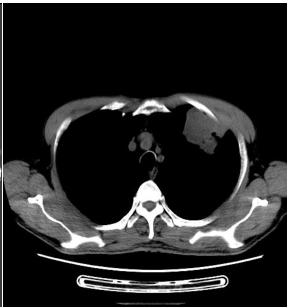

男, 67岁 既往“血小板增多症”2年,控制效果可。否认其他病史。影像学:CT示左肺上叶前段占位,大小5.5*5cm,破坏左侧第一前肋骨。手术所见:左肺上叶前段肿物,直径约5cm,同前胸壁关系密切并粘连,部分累及胸膜,遂行左肺上叶切除术。 |

| 影像学检查:(点击查看大图) |